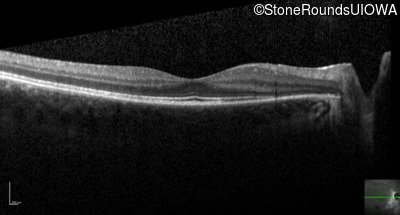

Optical Coherence Tomography - Right - 20/20

Exemplar / OCT Stack